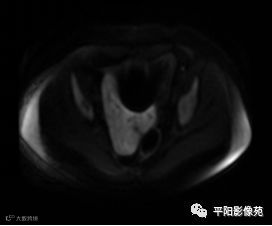

MRI表现

T2抑脂序列轴位

(宫腔内见金属节育环伪影)宫颈区见不规则形等T1稍长T2信号软组织肿块,DWI序列呈明显高信号,大小约为3.87cmX2.64cm,双侧宫颈基质低信号环连续性中断,病灶向子宫右后上方生长,周围脂肪间隙模糊,增强扫描明显强化,强化程度低于子宫及宫颈实质;子宫后方、子宫直肠间隙见不规则形长T1长T2信号软组织肿块,DWI序列呈高信号,大小约10.12cmX4.82cmX10.29cm,病灶呈分叶状,向下方生长与宫颈分界不清,与直肠分界尚清,增强扫描明显不均匀强化。